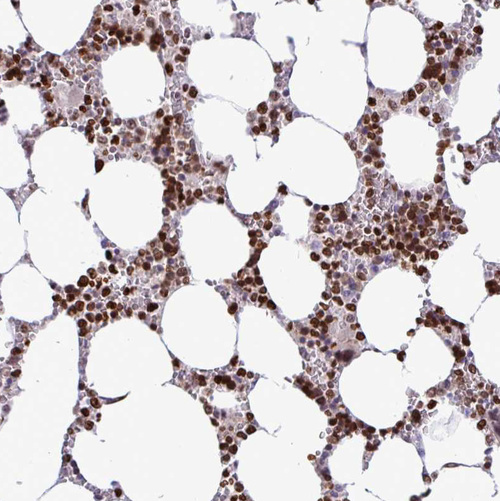

Immunohistochemistry analysis in human bone marrow and skeletal muscle tissues using HPA053314 antibody. Corresponding HMGB2 RNA-seq data are presented for the same tissues.